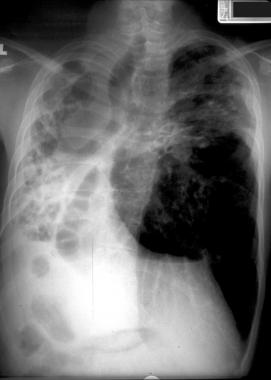

患有轻度肺部疾病的囊性纤维化患者的胸片可能正常。由于黏液堵塞而导致的肺部过度充气可能是儿童或成人时期的唯一表现。

中度或晚期时的肺部可能出现线状阴影和散在结节,并可能观察到节段性、斑片性或小叶性肺不张,儿童比成人更为多见,通常表现在右上叶。

图1 患囊性纤维化的青年男性,显示过度充气和上叶支气管扩张。